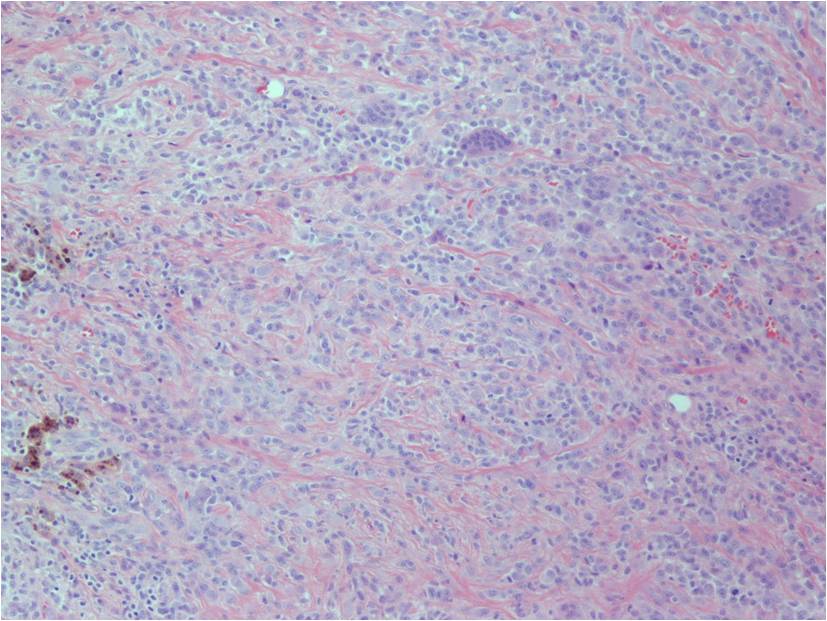

Microscopic (Fig. 12-14)

- Highly cellular

- Lipid Laden Macrophages

- Small polygonal

- Scant cytoplasm

- Spindled cells (with pale cytoplasm)

- Xanthoma cells

- Multinucleated giant cells

- Prominent chronic inflammatory cells

- Foams cells are observed in the periphery of the lesions.

- Hemosiderin pigment prominent

- Stromal and fibroblast cell proliferation

- Numerous cleft-like (alveolar) spaces

- Variable degree of villous, nodular and pigmentation (hemosiderin) and inflammatory components

- Frondlike synovial projections

- Both forms of the tumor are associated to a translocation t(1;2)(p13;q37) with a CSF-COLA3 gene fusion.

Fig. 12-14: Highly cellular sheet of spindled cells, multinucleated giant cells and chronic inflammatory cells with variable degree of pigmentation (hemosiderin). Numerous cleft-like spaces or ‘pseudoglandular’ spaces, surrounded by xanthoma cells. Cleft-like spaces are commonly seen in diffuse-type giant cell tumors.